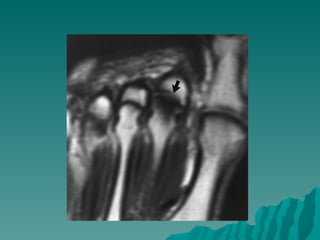

Keinböck hastalığı

 Genellikle

yetişkinlerde ve

unilateral

 El bileğinde ağrı ve

r          Travmalar ve

tekrarlayan

mikrotravmalar

Rober Kienböck (1871 -1953)     suçlanır.

 X-Ray: lunat kemikte

yaygın opasite

kemikte yassılaşma,

fregmantasyon

Keinböck hastalığı  Genellikle yetişkinlerde ve unilateral  El bileğinde ağrı ve hassasiyet r  Travmalar ve tekrarlayan mikrotravmalar Rober Kienböck (1871 -1953) suçlanır.  X-Ray: lunat kemikte yaygın opasite kemikte yassılaşma, fregmantasyon